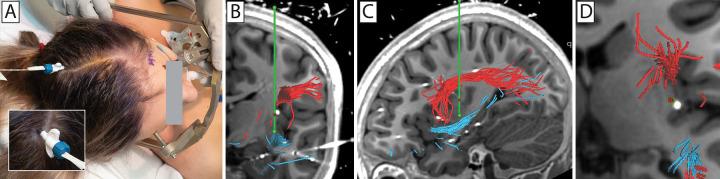

Open surgical treatment of insular epilepsy holds particular risk of injury to middle cerebral artery branches, the operculum (through retraction), and adjacent language-related white matter tracts in the language-dominant hemisphere. Magnetic resonance imaging (MRI)-guided laser interstitial thermal therapy (LITT) is a surgical alternative that allows precise lesioning with potentially less operative risk. The authors presented the case of a 13-year-old girl with intractable, MRI-negative, left (dominant hemisphere) insular epilepsy that was treated with LITT. Diffusion tensor imaging (DTI) tractography was used to aid full posterior insular lesioning in the region of stereo electroencephalography-determined seizure onset while avoiding thermal injury to the language-related superior longitudinal fasciculus (SLF)/arcuate fasciculus (AF) and inferior fronto-occipital fasciculus (IFOF).

DTI tractography was used successfully in planning insular LITT and facilitated a robust insular ablation with sharp margins at the interfaces with the SLF/AF and IFOF. These tracts were spared, and no neurological deficits were induced through LITT.

Although it is technically demanding and has important limitations that must be understood, clinically available DTI tractography adds precision and confidence to insular laser ablation when used to protect important language-related white matter tracts.